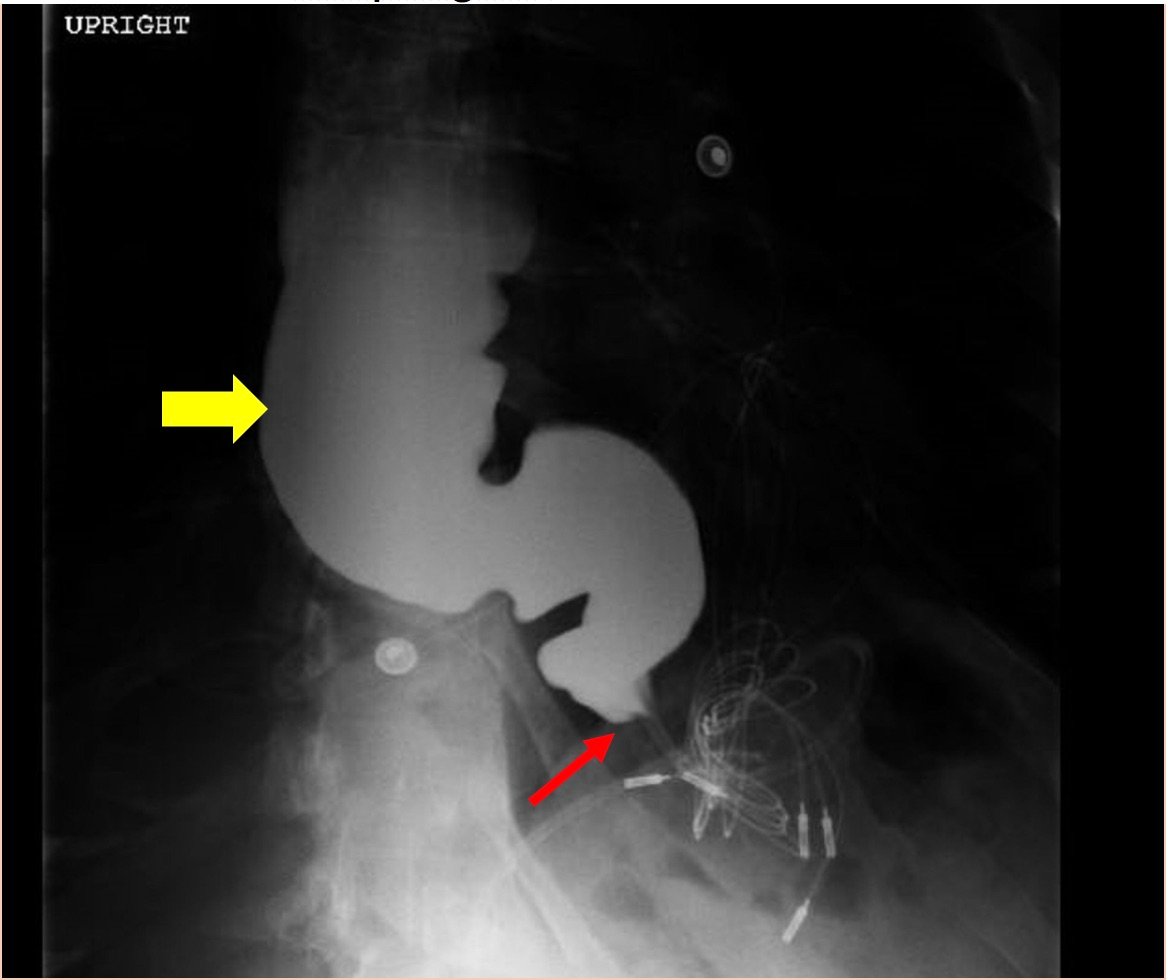

The chest X-ray demonstrated a markedly widened mediastinum (red brackets), raising concern for thoracic aortic aneurysm/aortic dissection, which prompted labs and contrast-enhanced computed tomography (CT) of the chest. The CT revealed a dilated proximal esophagus that narrowed distally (yellow tracing and red arrow), with particulate material, mass-effect on the trachea (purple outline), and bilateral patchy opacities suggesting aspiration. Barium esophagram showed a drastically dilated esophagus filled with contrast (yellow arrow), terminating into the classic “bird’s beak sign” (red arrow) at the lower esophageal sphincter (LES). Esophageal manometry later confirmed achalasia, proving that widened mediastina can have unexpected etiologies.

Achalasia is a rare (prevalence ~0.3-9.5/100,000, increasing with age) digestive disorder characterized by denervation to the distal esophagus, promoting regional aperistalsis and tonic contraction of the LES.1-3 Achalasia most commonly presents as acute, simultaneous dysphagia to both solids and liquids, but can present as heartburn, regurgitation, or even unexplained cough.1-3 A dilated esophagus with narrowing at the LES (“Bird’s Beak Sign”) and delayed esophageal emptying on barium esophagram are pathognomonic for achalasia (sensitivity 90%, specificity 95%),4 as is distal aperistalsis with increased resting LES tone on high-resolution manometry (sensitivity 98%, specificity 96%).5 Pharmacologic LES relaxation may be trialed, but surgical myotomy is usually necessary.1,2,3,6 Our patient underwent laparoscopic Heller myotomy resulting in a dilated, aperistaltic esophagus with no evidence of obstruction and is being followed for continued GERD and dysphagia.